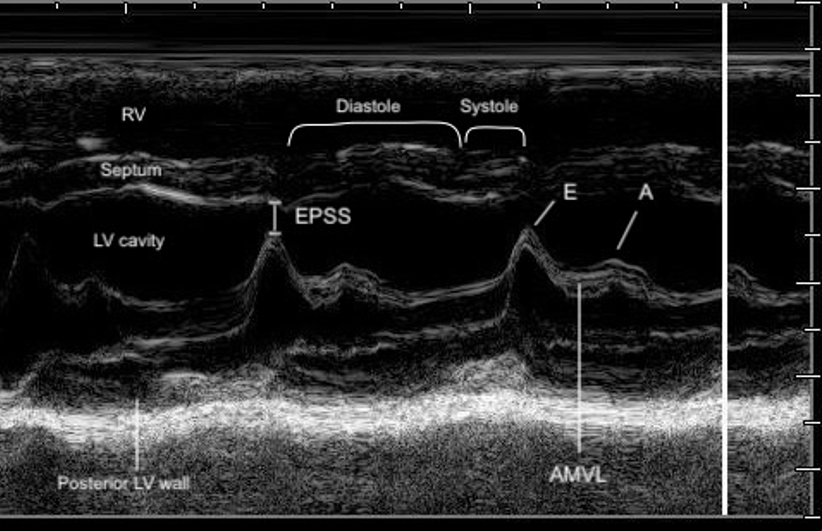

In the PLAX view, M-mode is commonly used to assess LVfx by placing the cursor perpendicular to the IVS and posterior wall at the level of the MV tips. This provides a time-motion trace of LV wall motion and cavity size throughout the cardiac cycle, with distance displayed on the y-axis and time on the x-axis allowing evaluation of systolic function.

You’ll see a wave-like motion tracing of the MV leaflets movement across the cardiac cycle. In early diastole, the AMVL rapidly opens toward the IVS, creating the tall E-wave, followed by a smaller A-wave from atrial contraction (figure 7,8).

End Point Septal Separation

The EPSS is a measure of AMVL motion and is used as a way to semi-quantify LVfx. It refers to the minimal distance between the peak of the E-wave and the IVS at the same X-axis time point (figure 8).

In a normally functioning LV, the E-point comes close to the septum (figure 9). In pediatric patients, there is limited validated evidence for normal EPSS values. A 1983 study provided guidelines for the use of EPSS in infants and children and found that normal EPSS was ≤ to 6mm, with 7-8mm being tail end of normal [21]. This was confirmed in a more recent study where an EPSS of 6.17 mm optimally distinguished normal from depressed LV systolic function, with a sensitivity of 86% and specificity of 92% [12].

The larger the EPSS distance the worse the function. Similar to the AMVL visual assessment, if the E-point is not close to the IVS during the M-mode tracing, this could suggest reduced systolic function. Specific cutoff values are available to guide interpretation (table 3) (Figure 10).